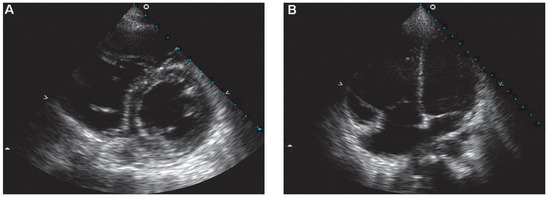

Hypertrophic Nonobstructive Cardiomyopathy as a Cause of Severe Restrictive Physiology

by Stéphane Noble, Caroline Frangos and Philippe L’Allier

66-year-old woman with a family history of hypertrophic cardiomyopathy (HCM) presented with severeprogressive exertional dyspnoea. She had recently complained of palpitations corresponding to atrial fibrillation on the ECG […] Full article

Figure 1